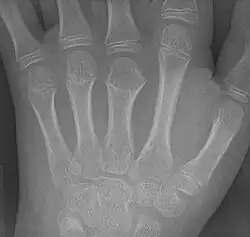

Brachymetacarpia

Brachymetacarpia or brachymetacarpalia is a medical condition in which the metacarpal bones of the hands are shortened.[1] The equivalent condition in the foot is brachymetatarsia, in which the metatarsal bones are shortened. Brachymetacarpia is typically congenital and presents in childhood or early adolescence, but it can also be associated with other acquired syndromes or endocrinological conditions. While cosmetic appearance is the most common concern of affected individuals, brachymetacarpia may also affect hand function due to alterations in muscle and tendon length. Treatment usually involves lengthening of the affected bone(s), either acutely with a bone graft or gradually with an external fixator.[2]

Prevalence of brachymetacarpia is unknown. The third, fourth, and fifth metacarpals are most commonly affected.[2]